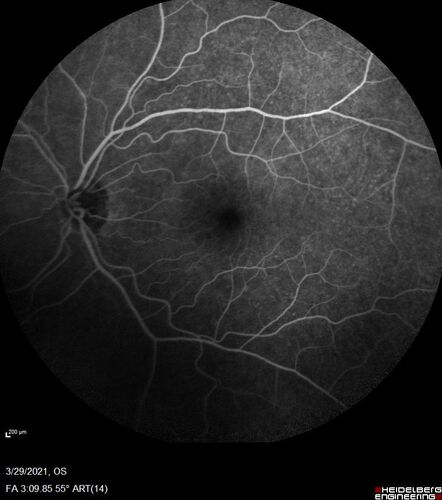

Ocular Lymphoma - Initially presented like auto-immune retinopathy

43 year old man: initial presentation - The vision in the left eye is blurry and opaque for about 2 weeks.  In the central of the vision, when he covers the right eye, in the center of the left eye there is a film with a light in the middle.  This has never happened before.  He has not been sick for the last few months.  A few weeks ago he saw waves on the floor when looking down but that has gone away.  Since the vision loss started the vision has not changed much.  The central vision is not getting better.

VA improved over 2 months to normal.  Then the patient had 2 more episodes of self-limited vision loss (no treatment).  Then 2 years later he presented with a diagnosis of CNS lymphoma and later developed subretinal deposits (last images)

lymphoma2_caflo_032021_36.jpg lymphoma2_caflo_032021_37.jpg lymphoma2_caflo_032021_38.jpg lymphoma2_caflo_032021_39.jpg lymphoma2_caflo_032021_40.jpg